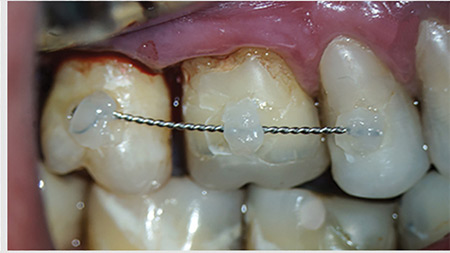

Pre-Orthodontic Periodontal Considerations: Establishing a Rationale and Timeline for Periodontal Intervention

Clear Aligners

Introduction: The proliferation of novel appliances in modern orthodontics, that are discreet or even completely undetectable, has encouraged a growing number of patients from adolescents to adults to seek out treatment. While referrals to an orthodontist are often made to address functional problems, esthetic reasons are an equal (if not more common) basis for addressing … Read more